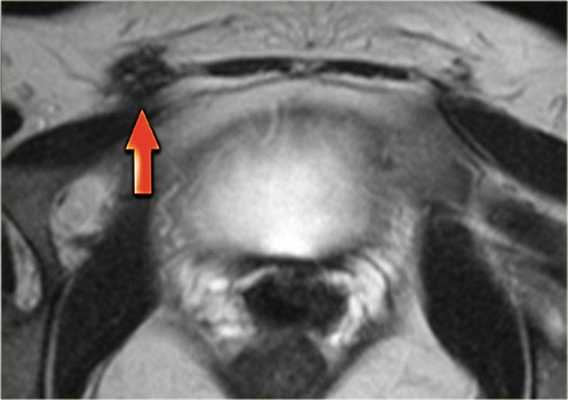

На аксиальной Т2 ВИ МР-томограмме продемонстрирован другой пример поражения брюшной стенки.